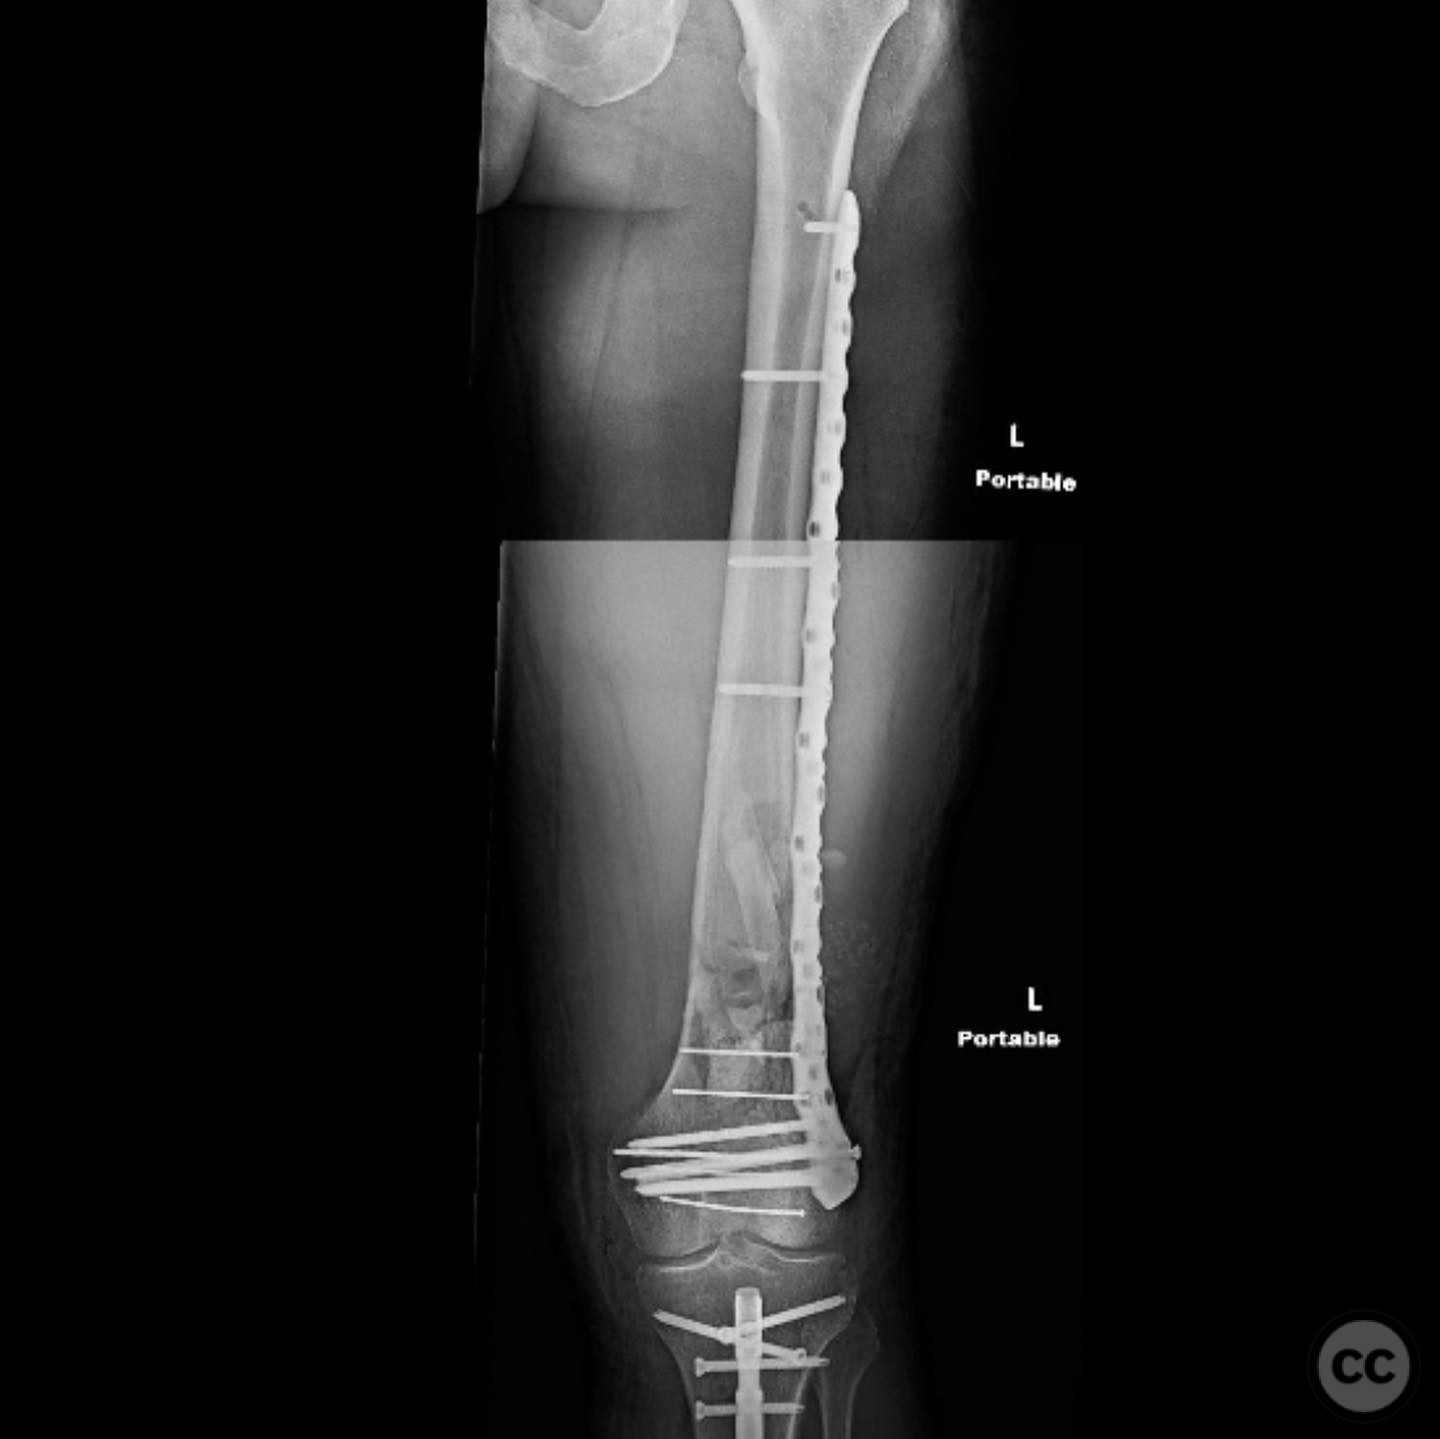

Clinical and radiological findings:  A 44-year-old male cyclist was involved in a collision with a car, resulting in open fractures of the distal femur and segmental tibia. The femoral fracture presented with a 4 cm transverse wound on the anterior aspect, while the tibial fracture had a 2 cm anterolateral wound at the distal site. There were no associated head, chest, or abdominal injuries, and compartment syndrome was not present. Vascular examination was unremarkable.

Anatomical surgical approach:  For the tibia, a longitudinal incision was made to access the proximal tibial start site for intramedullary nailing. Percutaneous clamps were utilized for reduction, supplemented by blocking screws as needed. For the distal femur, an external fixator was applied initially, followed by an in situ lateral approach for plating after reduction was achieved.

The tibial nailing required precise identification of the start site under fluoroscopic guidance, with percutaneous clamps aiding in reduction. Blocking screws were considered but not necessary due to successful reduction with clamps alone. The distal femur presented challenges in achieving coronal and sagittal alignment, necessitating reliance on the external fixator for reduction before proceeding with plating.

Postoperative protocol:   Postoperative rehabilitation included early mobilization with weight-bearing as tolerated on the tibia, while the femur required protection until definitive fixation was achieved. Progressive weight-bearing was introduced following femoral plating.

Orthopaedic implants used:   Intramedullary nail for tibia, external fixator for initial femoral stabilization, and locking plate for definitive femoral fixation.